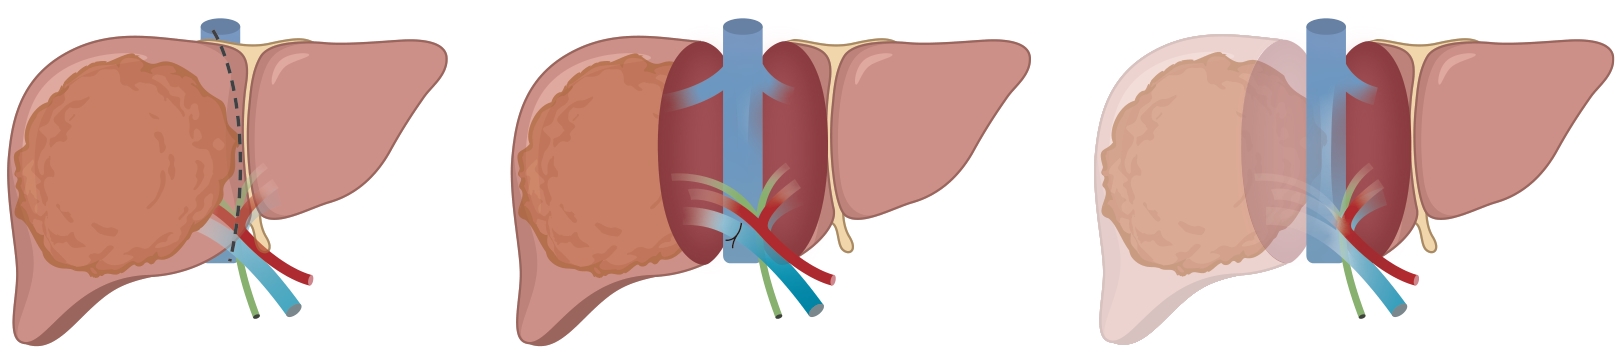

巨大自发性脾肾分流道栓塞联合抗凝治疗门静脉血栓1例报告

门静脉血栓是肝硬化患者常见且严重的并发症,门静脉血流动力学的改变与门静脉血栓的发生密切相关。合并巨大的自发性脾肾分流时门静脉灌注减少、血流速度减慢,极有可能削弱门静脉血栓的抗凝效果。本文将报道1例通过栓塞自发性脾肾分流道联合抗凝治疗策略,实现了门静脉的完全再通,然而,仍需高质量的临床研究进一步验证和支持这一策略的有效性。